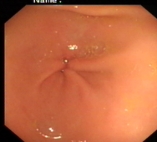

正常胃表现

内镜下表现:黏膜红白相间,以白色为主,黏膜皱襞变平或消失,部分黏膜血管显露,可伴有黏膜颗粒或结节状等表现。如伴有肠化生于电子染色窄带成像放大内镜(NBI ME)下发现胃粘膜上皮细胞表面的脑回样结构嵴部的纤细浅蓝色线样结构。病理活检可进一步确诊。